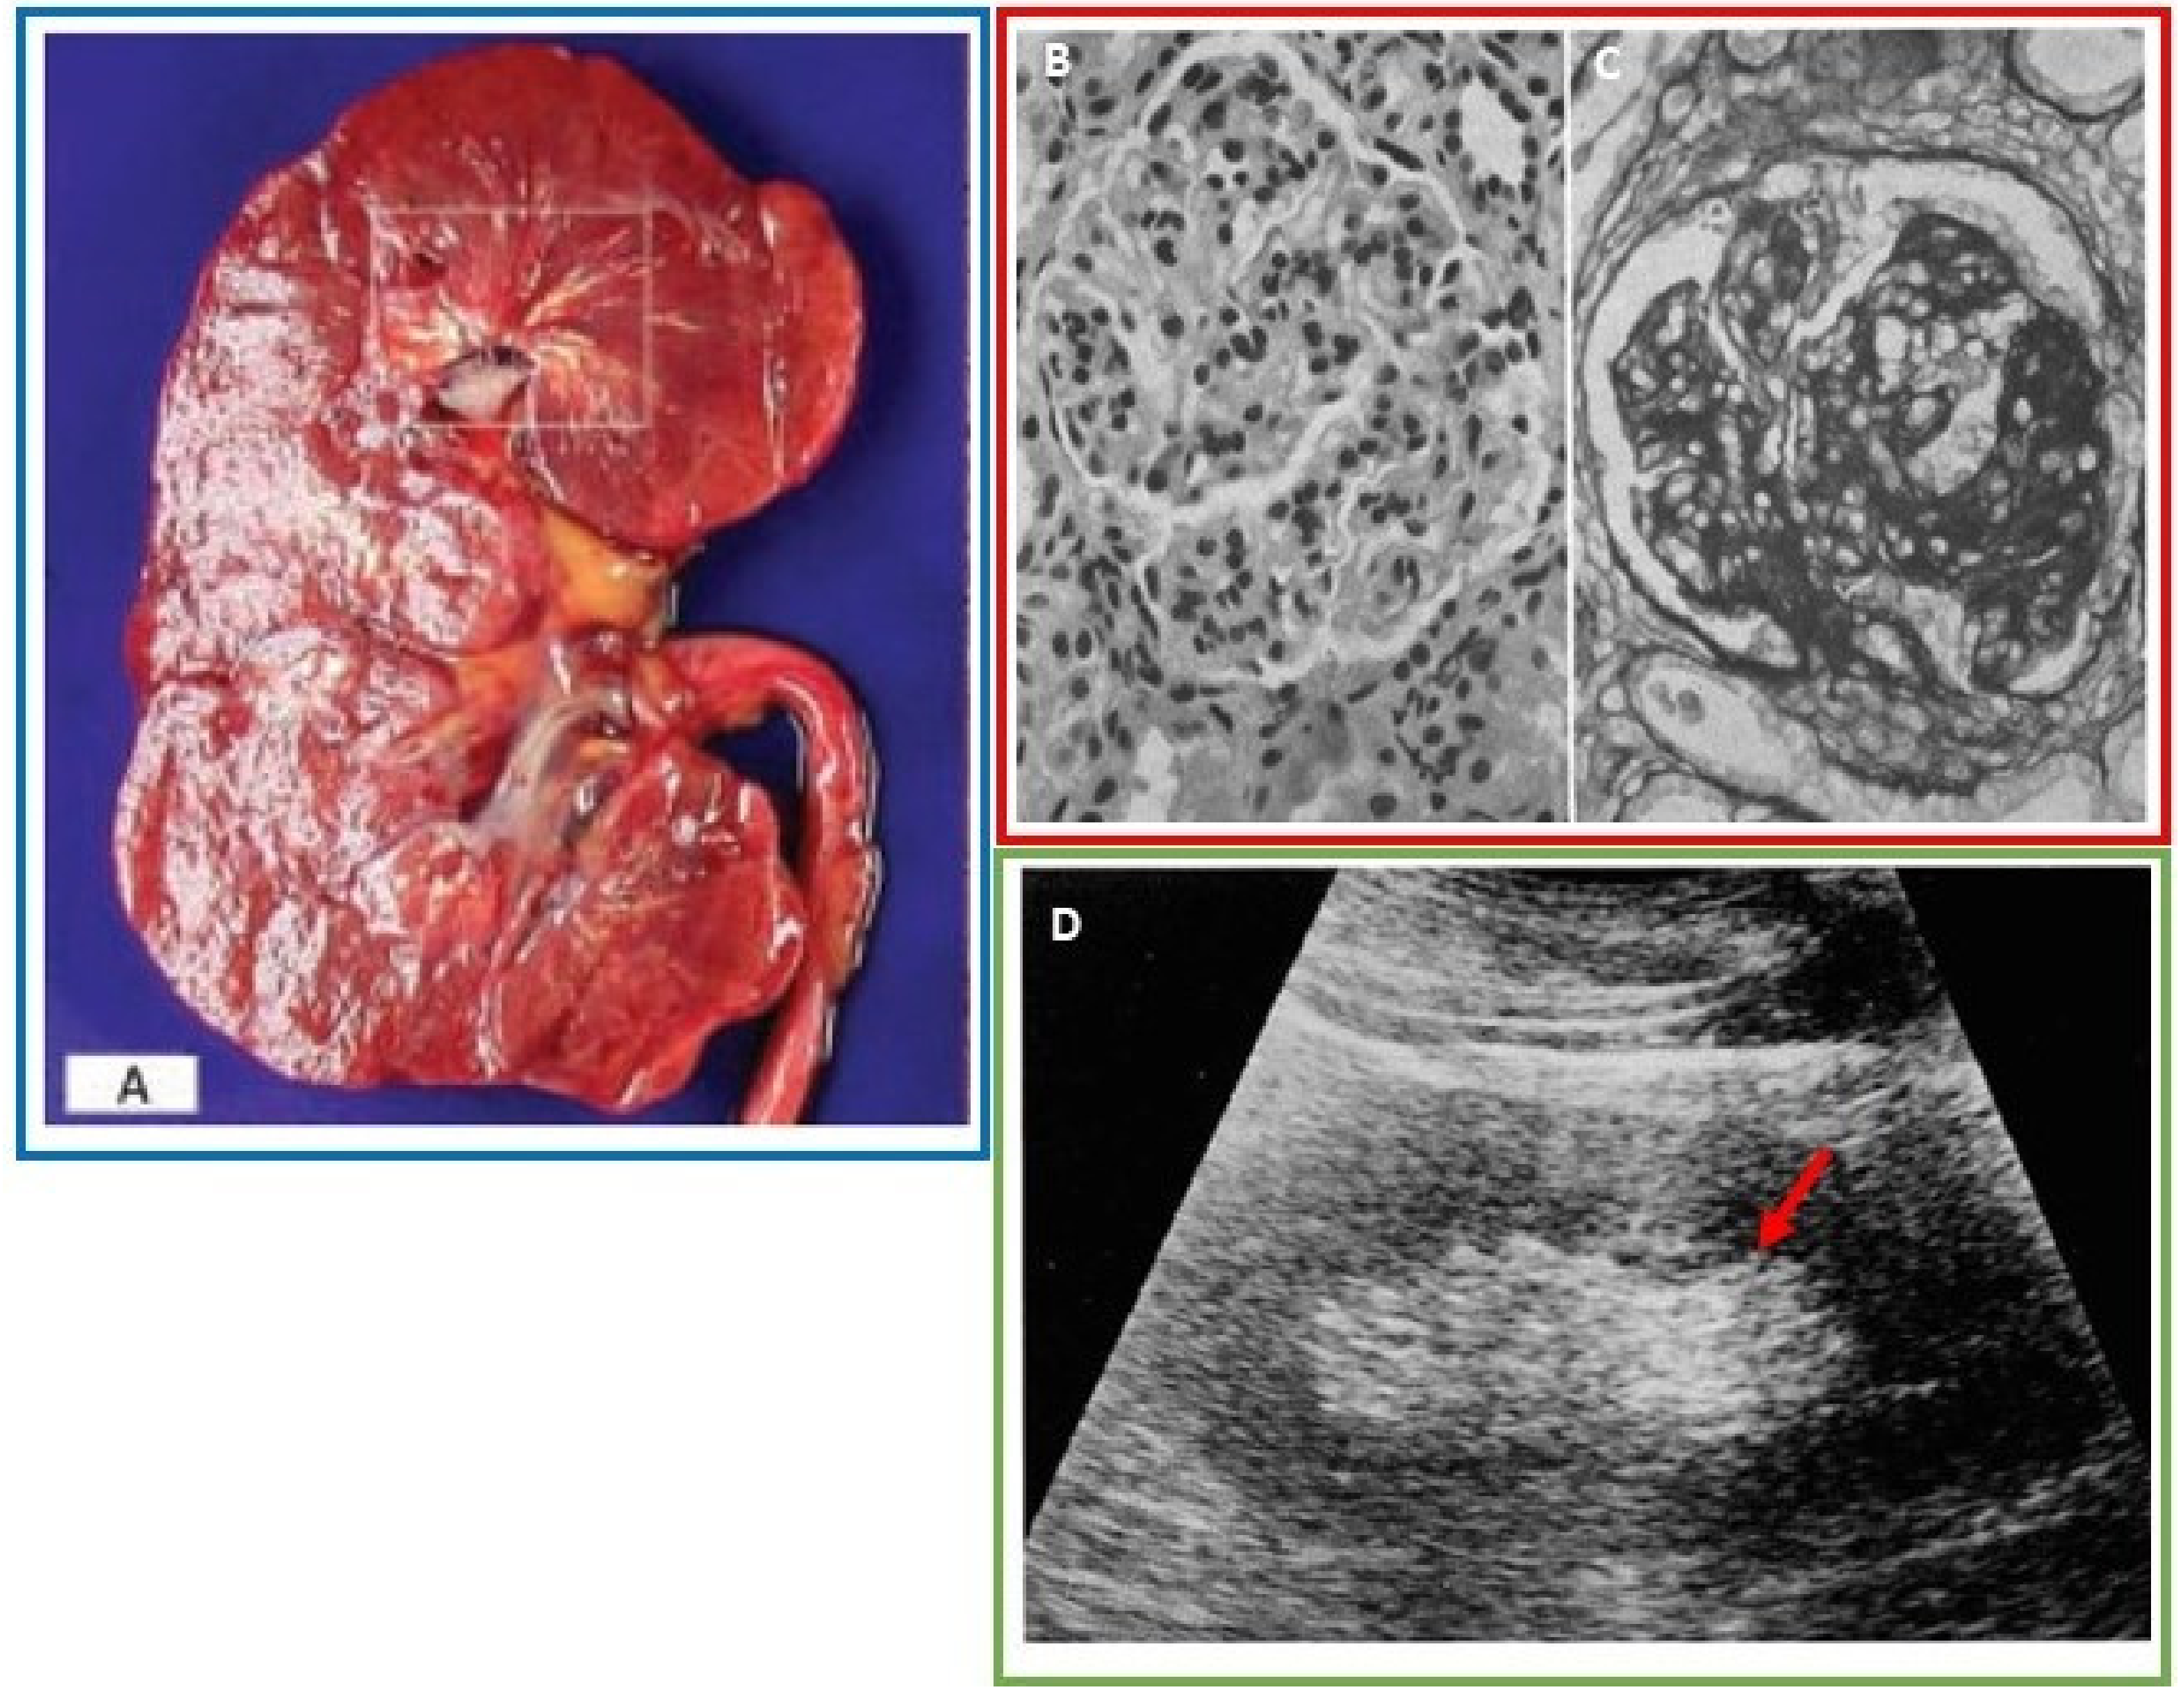

- Ayoub, I.; Almaani, S.; Brodsky, S.; Nadasdy, T.; Prosek, J.; Hebert, L.; Rovin, B. revisiting medullary tophi: A link between uric acid and progressive chronic kidney disease? Clin. Nephrol. 2016, 85, 109–113. [Google Scholar] [CrossRef]

- Linnane, J.W.; Burry, A.F.; Emmerson, B.T. Urate deposits in the renal medulla. Prevalence and associations. Nephron 1981, 29, 216–222. [Google Scholar] [CrossRef]

- Lichtenstein, L.; Scott, H.W.; Levin, M.H. Pathologic changes in gout; Survey of eleven necropsied cases. Am. J. Pathol. 1956, 32, 871–895. [Google Scholar]

- Kim, M.Y.; Jeon, W.K.; Kim, H.K.; Kirn, Y.S.; Han, C.Y.; Kim, Y.T.; Han, S.T.; Lee, Y.W. Sonographic findings in gouty nephropathy. J. Korean. Radiol. Soc. 1994, 31, 523–527. [Google Scholar] [CrossRef][Green Version]

- Bardin, T.; Tran, K.M.; Nguyen, Q.D.; Sarfati, M.; Richette, P.; Vo, N.T.; Bousson, V.; Correas, J.-M. Renal medulla in severe gout: Typical findings on ultrasonography and dual-energy CT study in two patients. Ann. Rheum. Dis. 2019, 78, 433. [Google Scholar] [CrossRef]

- Toyoda, K.; Miyamoto, Y.; Ida, M.; Tada, S.; Utsunomiya, M. Hyperechoic medulla of the kidneys. Radiology 1989, 173, 431–434. [Google Scholar] [CrossRef]